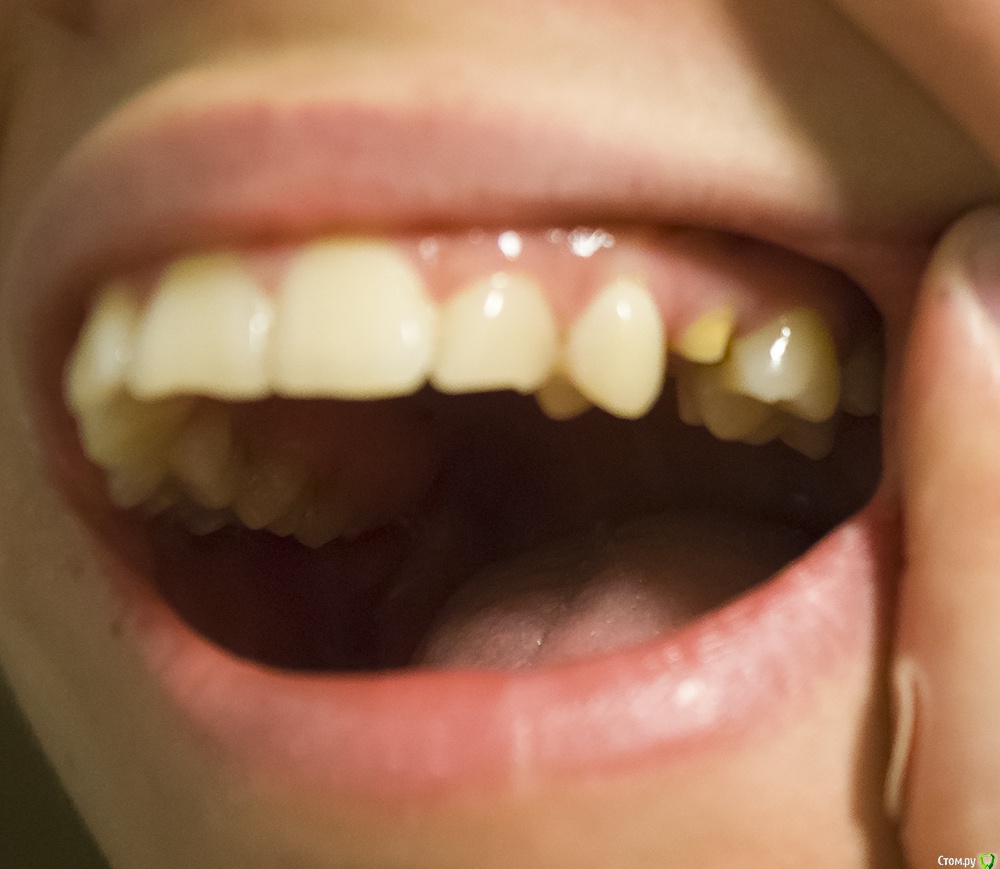

Здравствуйте.

Сломана левая верхняя 5, восстановлению не подлежит, естественно, предлагают имплантацию. А у меня с этой стороны ретинированный клык. Возможно ли вместо имплантации вытащить этот клык, дав сместиться 4 на место 5?